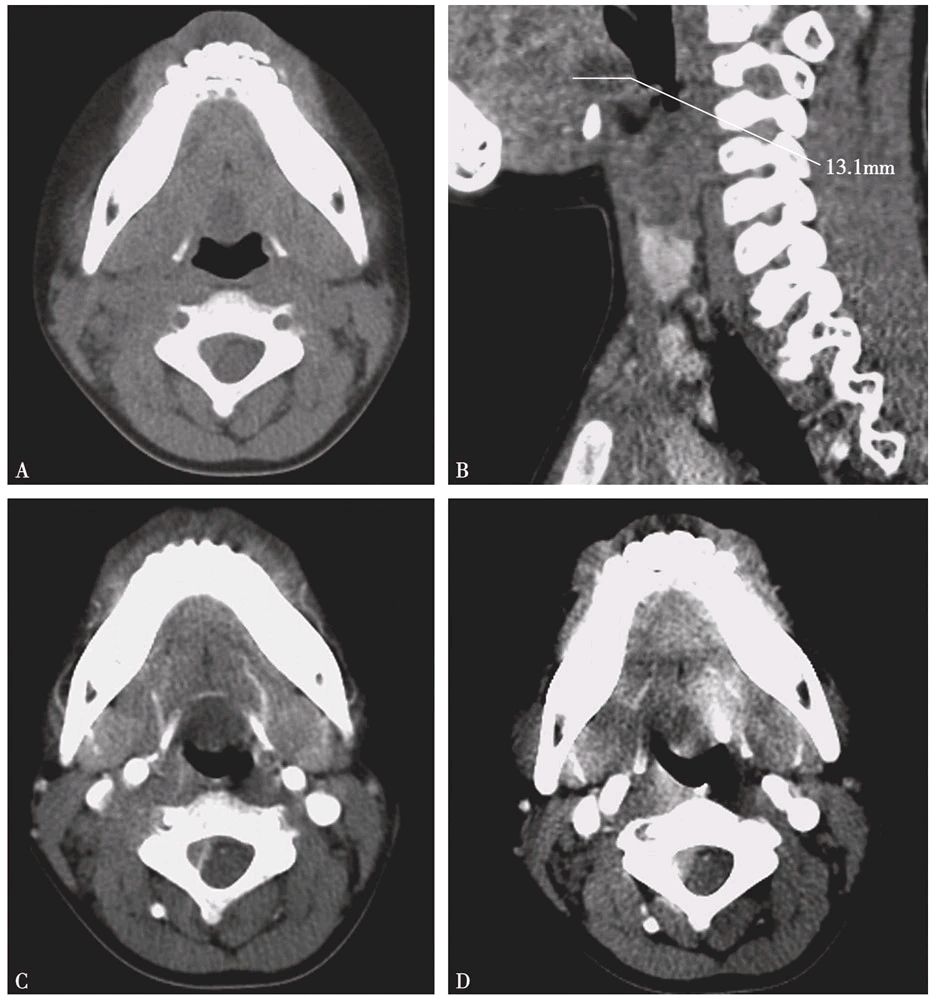

③CT通常表现为边界清楚、类圆形或椭圆形的低密度影,偶见分隔,边缘可强化。继发感染时,囊肿密度可接近软组织密度。MR T1WI表现为低至高信号,T2WI通常为高信号,增强后其内容物不强化,边缘可出现程度不一的强化。